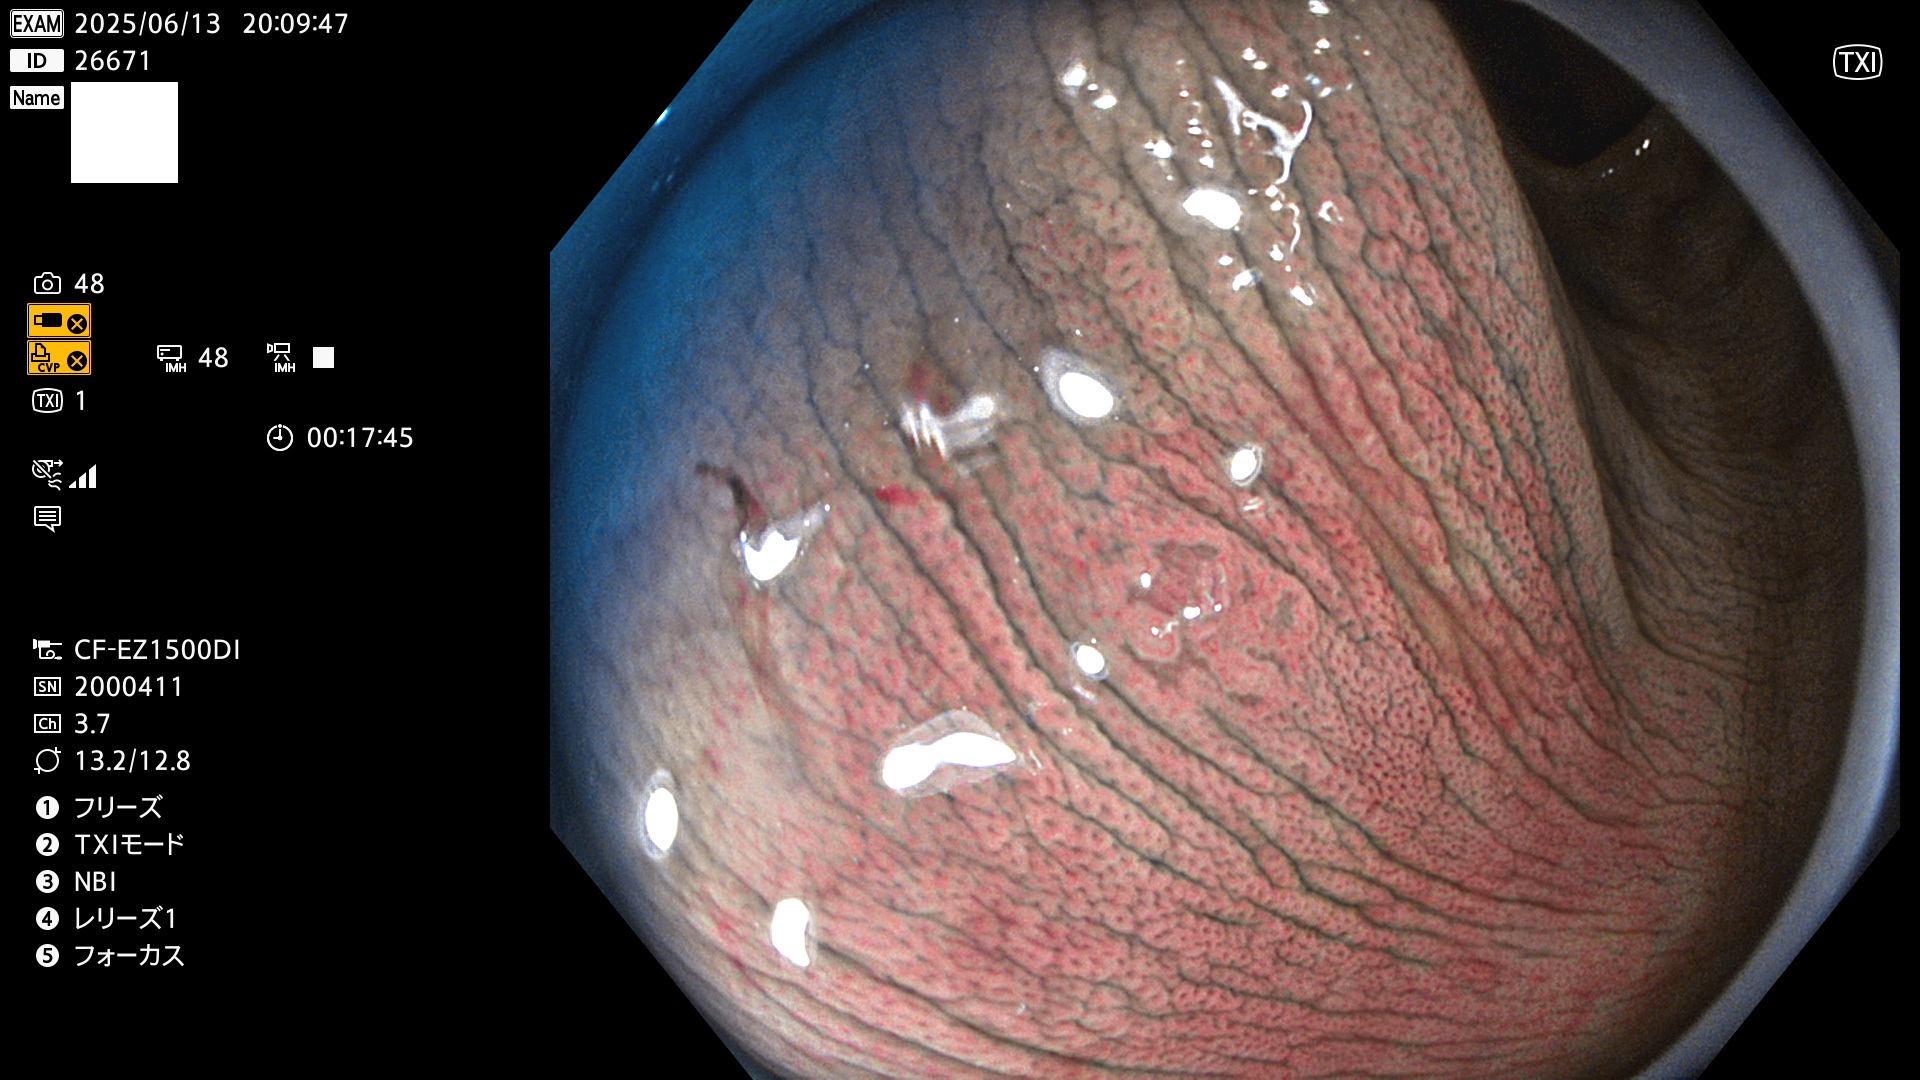

完全に平坦な物をUb、陥凹している物をUcと呼びます。Ubは認識が困難で、Ucはびらん(炎症)と紛らわしいために見落とされやすく、「内視鏡後・大腸癌」の原因になります。

抽出の対象期間 2025年6月12日〜6月15日の4日間(48件の検査)14個 (14/48=29%)